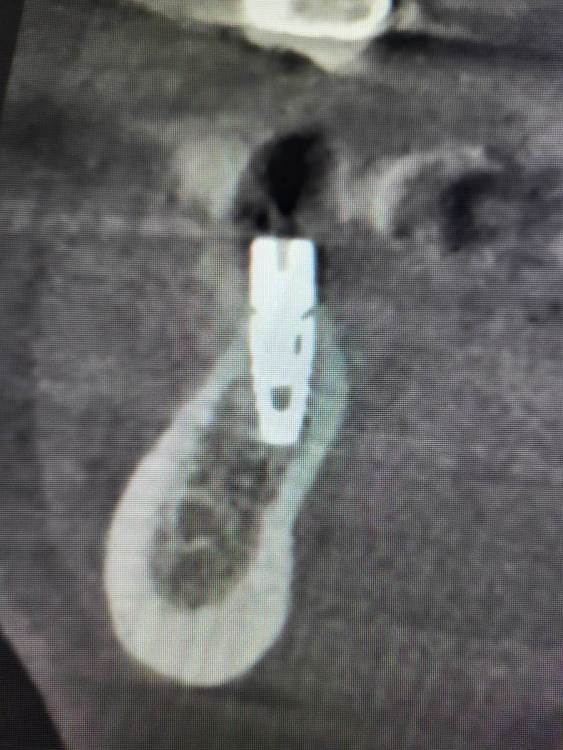

Irouil Опубликовано 28 ноября, 2023 Поделиться Опубликовано 28 ноября, 2023 Дорогие коллеги, прошу советов и мнений Пациентка 52 лет, соматика без особенностей В мае 2023 установлен имплант в позицию 3.5, первый срез КТ - на момент установки. В августе был утерян ФДМ, установил другой, снимок на момент обращения с незначительной резорбцией В ноябре пациентка пришла протезироваться, у винта выраженная щелевидная резорбция язычно и кратерообразная - параплатформенно Три других винта, установленных в то же время (но без головняка с ФДМ) выглядят более чем удовлетворительно Что скажете? P.S. поперечный срез КТ выставлен на уровне платформы импланта Ссылка на комментарий

Irouil Опубликовано 28 ноября, 2023 Автор Поделиться Опубликовано 28 ноября, 2023 29 минут назад, АнтонТЛТ сказал: Фдм упёрся в кость язычно, кость от сдавления рассосались, фдм расшатался и начал подсасывать слюну. А потом совсем выпал. Все так, но вопрос не в этом Вопрос в том, почему резорбция усилилась после установки ФДМ и какой выбрать план действий? Я периодически наблюдаю реминерализацию тканей в таких дефектах после фиксации протетики, но только на конусах. С другой стороны, глубокий дефект здесь достаточно узкий и только в одном месте, окружён хорошими стенками. Не хочу проводить имплантопластику (по мне уже проще переустановить, если винт не запротезирован), но надкостнично думаю провести небольшой кюретаж (по краям костных стенок дефекта), поменять ФДМ на новый и дать время. P.S. есть ещё снимок сразу после рефиксации ФДМ, там картина в разы лучше (собственно, он сделан в тот же день, что и снимок без ФДМ) Ссылка на комментарий